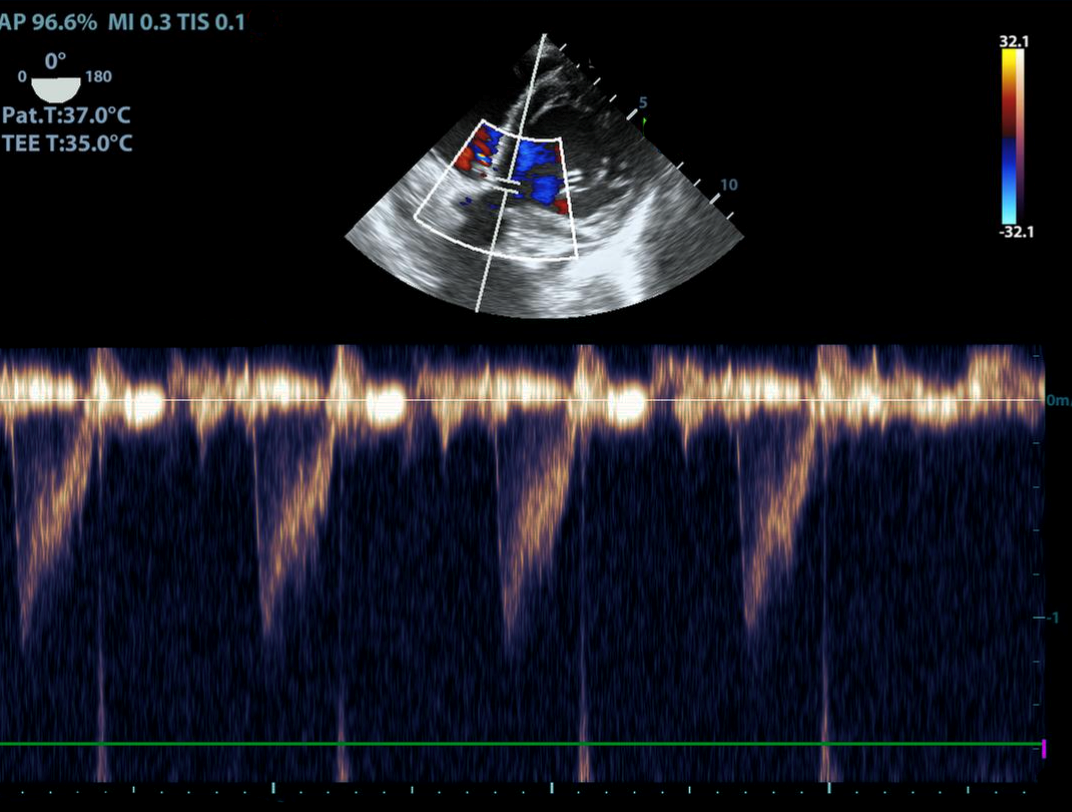

TEE Resus VTI - No Measurement Image